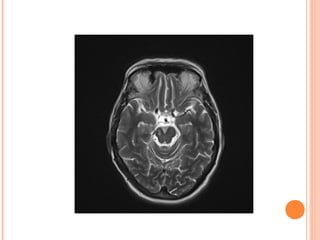

Normal Abnormal

[123I]FP-CIT SPECT (DAT SCAN) NormalAbnormal caudate putamen